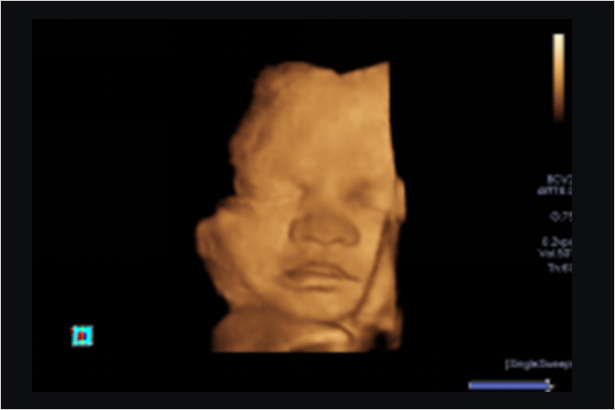

一整套完备的解决方案,具有全面的成像模式,包括表面成像,断层切面成像和多平面重建成像等